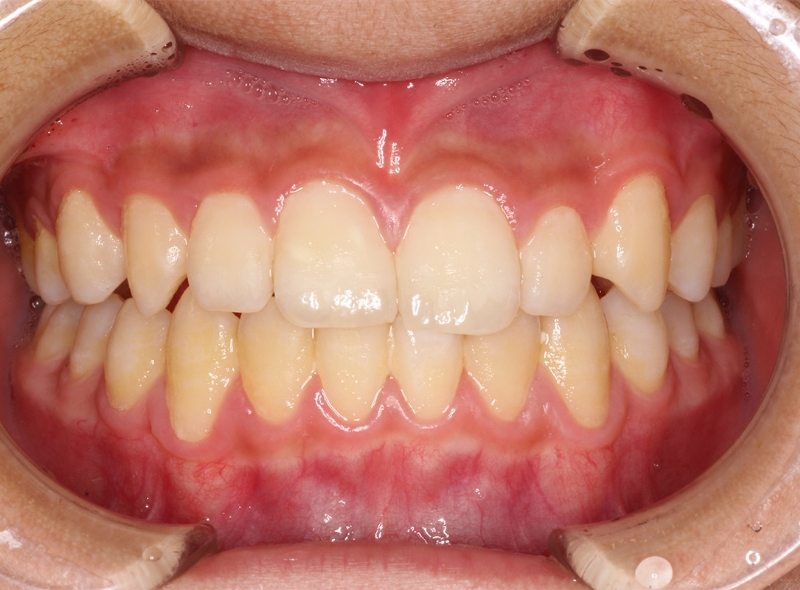

CASE 小児の矯正(叢生)

Before

After

| 年齢 | 11歳(治療開始時) |

|---|---|

| 性別 | 男性 |

| 症状 | 叢生(歯並びがガタガタしている) |

| 治療法 | |

| 費用 | 495,000円(税込み) |

| 通院回数 | 症例による |

| リスク・副作用 | 特になし |

| 備考 | やや遅い治療開始ではあったが、本人の頑張りによりブラケット(ワイヤー)を使わず、歯も抜かずに治療完了。 |